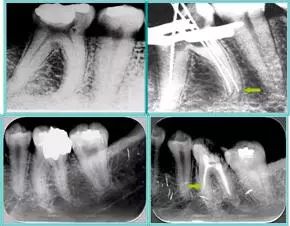

5. 不良根管充填物

常见不良根管充填物有干髓、塑化、塑化 + 根充和不良根充。

牙胶尖什么颜色​牙齿“晓”“技”|最全根管治疗的标准步骤,以及细节把握_https://www.jmylbn.com_新闻资讯_第21张

( 1 )干髓。

干髓治疗时,开髓后髓腔里注入甲醛甲酚 FC 灌髓,三聚甲醛固定,髓室底放置三聚甲醛缓慢释放,进行根管无害化处理。髓腔缓慢坏死,机体代偿出现根管钙化。如果患者在封闭腔出现出现病变,由于髓腔钙化,根管堵塞严重,检查治疗比较困难。

解决方法:1 )彻底去除坏死的牙髓组织。2 )借助化学性药剂,如 EDTA 等。3 )初锉选用8#或10#K 锉,平衡力法探察到工作长度 , H锉上下提拉法使根管扩大,提高工作效率。

牙胶尖什么颜色​牙齿“晓”“技”|最全根管治疗的标准步骤,以及细节把握_https://www.jmylbn.com_新闻资讯_第22张

左图和上图为干髓治疗后牙齿,龋齿疏通后进行根管充填。

( 2 )塑化。

传统的治疗思维:塑化治疗后患者需将塑化液清理干净,达到彻底根管治疗目的。 牙胶尖什么颜色​牙齿“晓”“技”|最全根管治疗的标准步骤,以及细节把握_https://www.jmylbn.com_新闻资讯_第23张

目前的治疗思维:以前塑化治疗效果好时不必清理干净塑化液。对于根尖没有病变的患者,可借助溶解剂建立通路;根尖存在病变的患者往往是塑化治疗不理想患者,需要彻底打通通路。